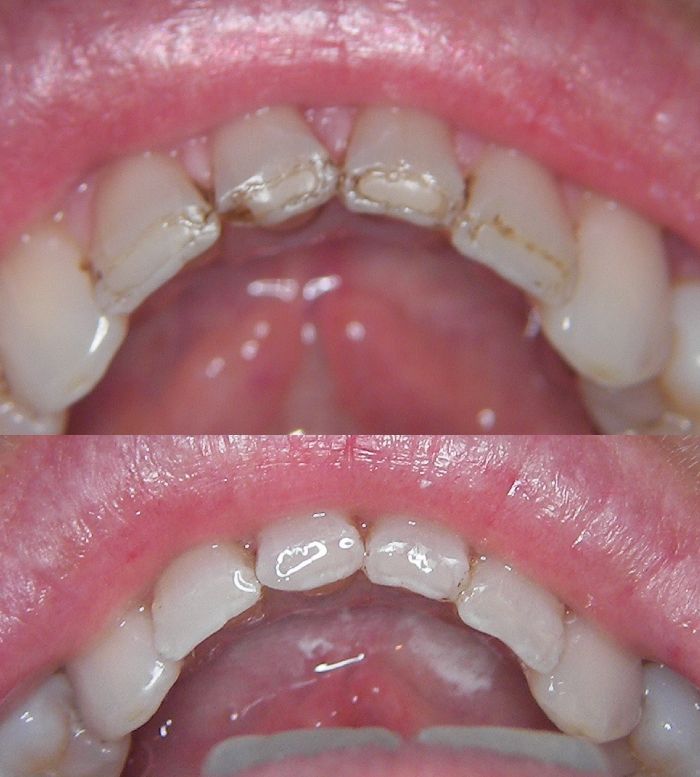

Can children as well as adults benefit from Air Abrasion?

Yes. Not only can I restore decayed teeth using this technology but also air abrasion is excellent for preparing a tooth prior to fissure sealant placement. These fissure sealants are “bullet proof” & do not fall out.